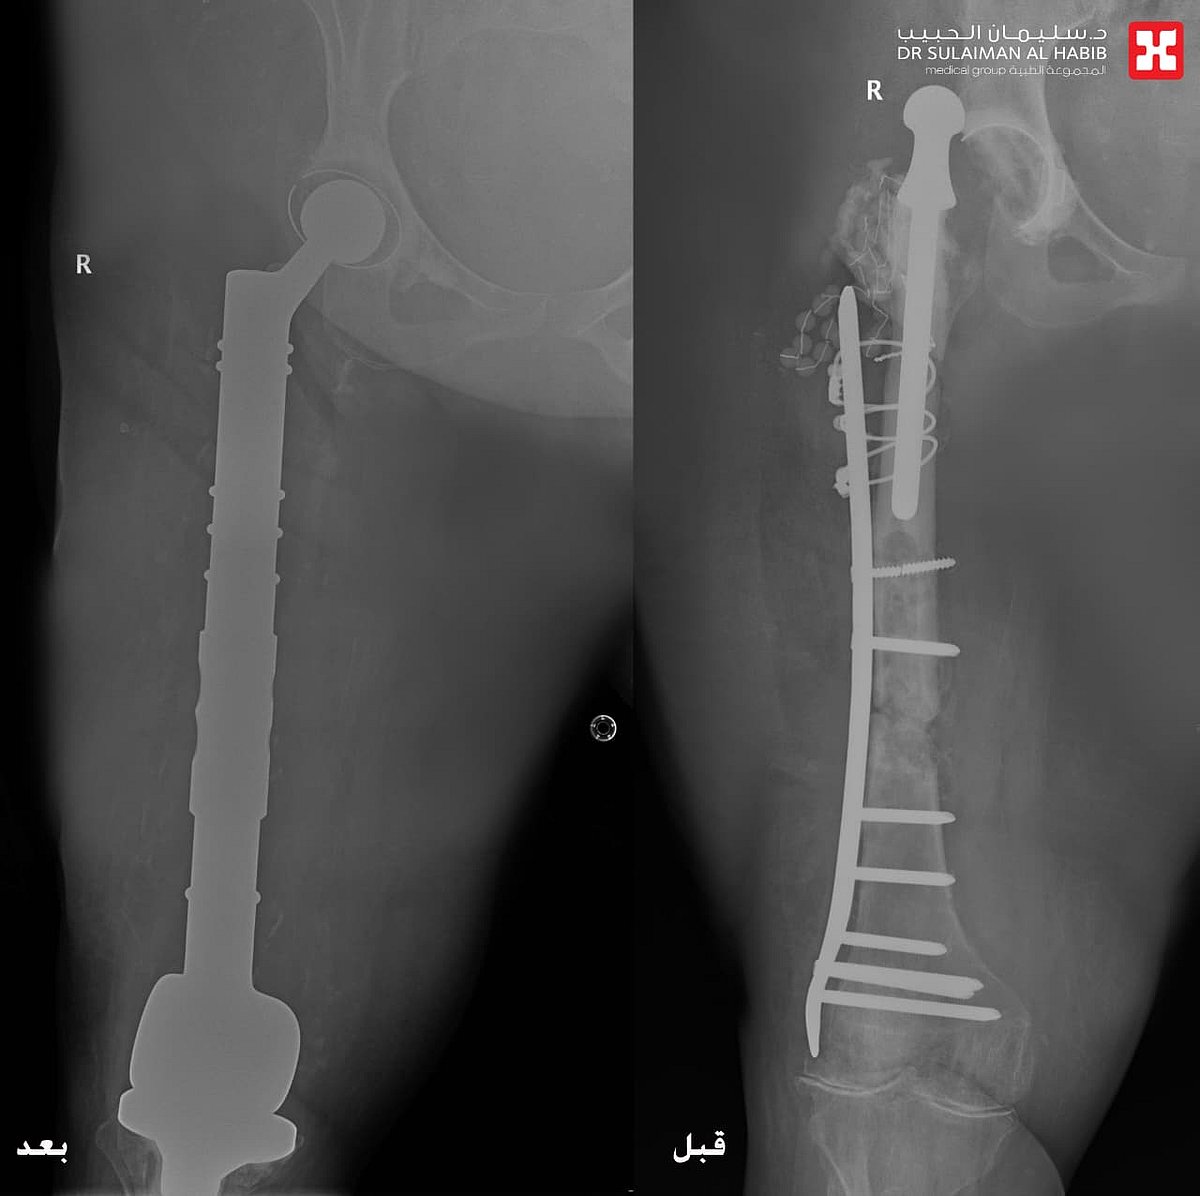

مستشفى الدكتور سليمان الحبيب بالخبر يستبدل مفصلي الركبة والورك وعظمة الفخذ ويزيل ورما وزنه “20” كجم ويعيد “الحركة” لـ”ستينية”

تمكن مستشفى الدكتور سليمان الحبيب بالخبر، من إعادة القدرة على الحركة والمشي لسيدة ستينية، ظلت طريحة الفراش منذ أكثر من 14 عاماً، بسبب مضاعفات عملية استبدال مفصل الورك الأيمن كانت قد خضعت لها قبل “30” عاماً، وأجرى لها فريق طبي قاده د. عبدالرحمن الرفاعي استشاري جراحة العظام وعظام الأطفال والتشوهات ومفصل الورك المتقدمة، جراحة معقدة وناجحة أنهت معاناتها.